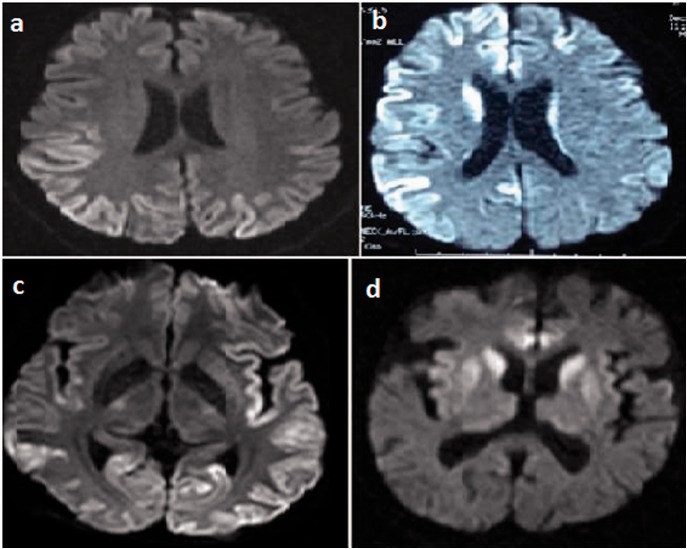

Results: Of 20 patients, 11 (55%) were men and nine (45%) were women. The mean age at disease onset was 60.0 ± 9.5 years (age range, 47-80 years). All patients without exception had characteristic abnormalities in DWI and/or FLAIR on admission, about 4 months after the initial symptom. Periodic complexes on EEGs characteristic for CJD were detected only in 10 patients (50%) on admission and in 13 patients (65%) during disease course. Out of 14 patients who underwent CSF examination, 11 (78.5%) were positive for 14-3-3 protein.

Conclusion: Although the definite diagnosis of CJD is made histopathologically, we aimed to discuss the value of magnetic resonance imaging in the diagnosis of CJD in respect to EEG findings and protein 14-3-3 levels in CSF.